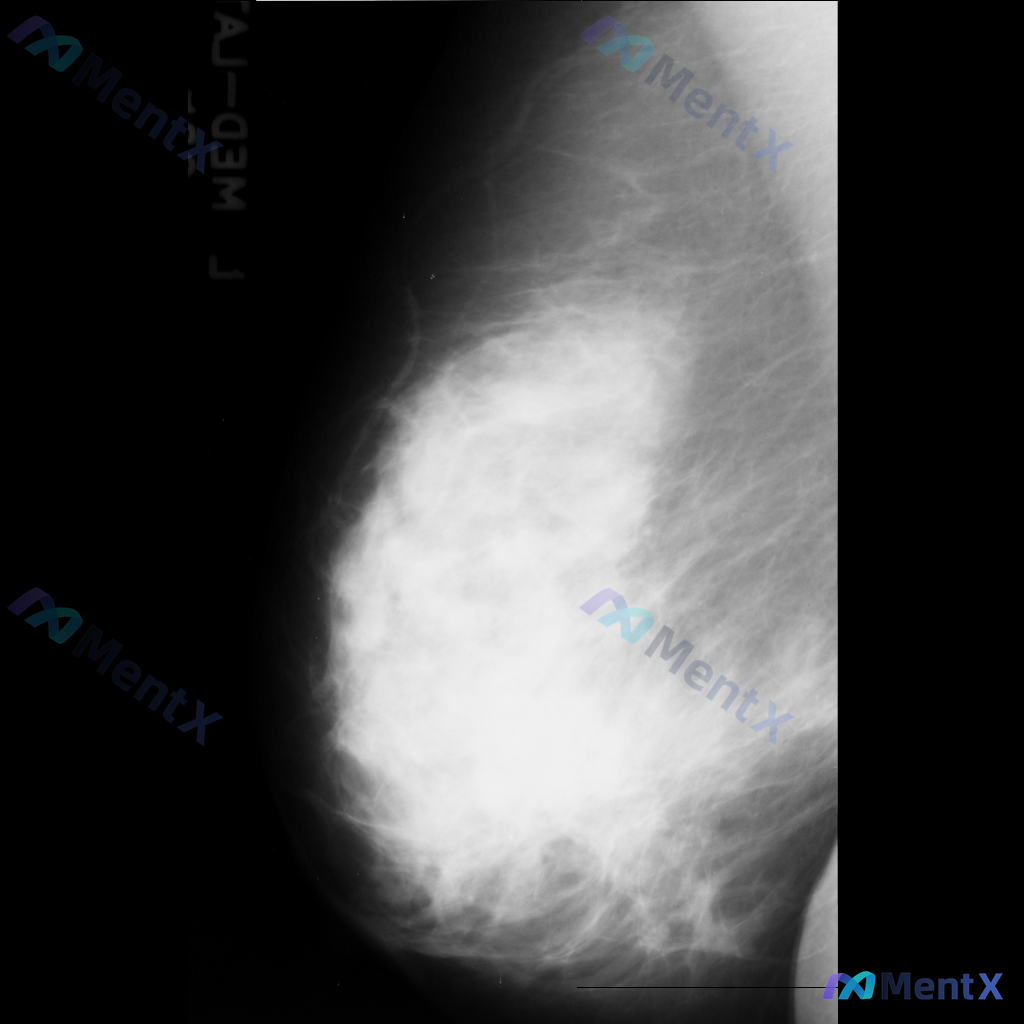

整理到一份右侧乳腺钼靶的影像资料,先和大家说一下表现: - 背景为不均匀致密型乳腺 - 右侧乳腺中部偏上区域可见局限性、成簇的细小多形性钙化 - 钙化区域周围可见局部密度略增高/结构异常的表现 目前还没有进一步的检查结果,单看这组影像表现,大家会优先往哪个方向考虑?后续评估思路是什么?